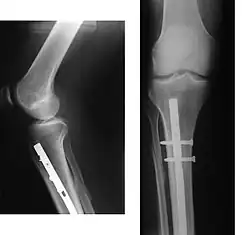

![]() | |

| Internal and external views of an arm with a compound fracture, both before and after surgery | |